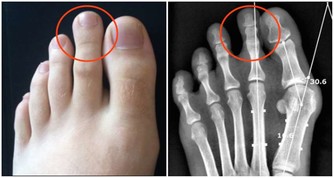

就目前已經明確的研究來看,肝癌的發生多與5個因素有關:

1、病毒性肝炎

在上述報告中也提到,中國肝癌的高病發率和慢性乙肝病毒關係很大,臨床數據顯示,肝癌患者中85%都有乙肝病毒感染經歷。也有研究指出,丙肝病毒比一般人群的肝癌風險增加15-20倍,而且未治療人群中有14.4%的肝癌風險。

種種數據都證實,想要預防肝癌,就一定要先解決病毒性肝炎的困擾:

- 患有慢性乙、丙的患者要積極治療

- 健康人群要及時接種乙肝病毒

- 患有肝炎的已婚人士在生育時要做好母嬰阻斷。

2、非酒精性脂肪性肝炎

脂肪肝在中國成年群體中的病發率高達20%,一般脂肪肝患者表面都十分健康,但後期若不注重干預和治療,可能從脂肪肝轉變成脂肪型肝炎,再到肝硬化,直到肝癌的出現。

4、黃曲霉素污染

黃曲霉毒素只有在280攝氏度的高溫下才會被破壞,如果處理不到位,持續微量進入人體就會造成慢性中毒,導致腎損傷,增加肝癌風險。研究發現,黃曲霉毒素在人體內的代謝產物會和乾細胞DNA結合,增加基因突變,也因此在黃曲霉毒素高發地區,肝癌患者也高達30-60%。

由此可見,黃曲霉毒素對人體,尤其是肝臟危害非常嚴重,一定要避免接觸,生活中要學會分辨黃曲霉毒素,發霉的食物直接扔掉,不要用自己的健康換取表面節儉,如果一些無法更換的東西有可能受到黃曲霉毒素污染,可以高溫殺菌。

5、水源污染

研究發現,污染的水源中所含有的有機苯、有機氯,水藻毒素等有促癌、致癌效果,尤其是池塘中常見的藍綠藻,是肝癌的高危因素之一。

生活中,一定避免接觸污染水源,更要學會少扔垃圾,保護水源,從根源上減少水源的污染,如果發現有藍綠藻的水源或污染嚴重的水源,及時上報相關部門,及時進行安全處理。